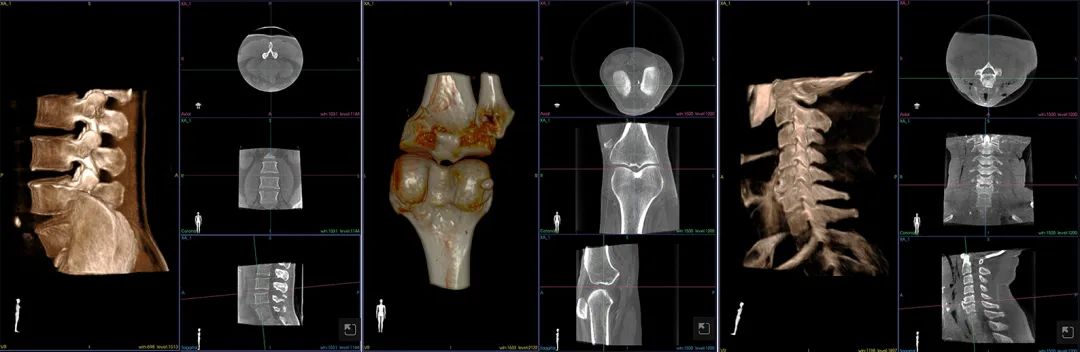

另外,劉新宇教授對(duì)歌銳術(shù)中CBCT也給予了高度評(píng)價(jià)。他表示,歌銳CBCT僅用12s~14s即可完成影像掃描及三維重建,節(jié)省了時(shí)間,圖像精度達(dá)0.16mm,滿足了外科精準(zhǔn)手術(shù)的需求,此外,偏心投照的設(shè)計(jì)十分人性化,為通道穿刺等臨床工作提供了便利。

專門開發(fā)的“牛頓”3D高精度術(shù)中CT可獲得超高精度影像,是微創(chuàng)手術(shù)規(guī)劃和執(zhí)行的基礎(chǔ)